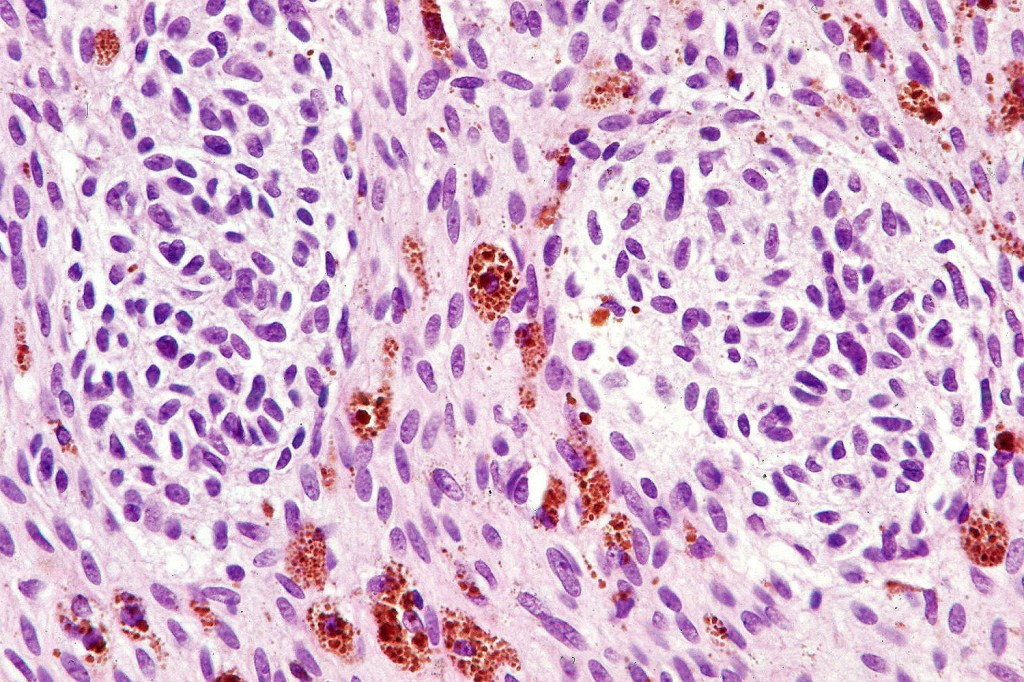

Cellular blue nevus

This uncommon most often devlops on the buttocks, sacrococcygeal region & distal extremities although it may be seen at just about any site. It shows a predilection for females and is diagnosed most often in the 2nd-4th decade. It presents as a blue-black/ or black nodule measuring 1-2 cm in dianeter. Similar to common blue nevus, the cellular variant can be encountered in a wide range of non-cutaneous locations.

Histological features

•Most characteristic is the dumbbell silhouette although a plague morphology may also be encountered

•Combined nevus variant

•Admixture of spindle cells, pigmented bipolar or dendritic cells & melanophages

•Cytoplasm is pale and nuclei are small with inconspicuous nucleoli

•An alveolar pattern is characteristic particularly with clear cell nodules

•Mitoses are typically very sparse or absent

•No atypical mitoses

•No Necrosis or lymphovascular invasion

•Multinucleate giant cells sometimes present

•Stromal fibrosis, myxoid change, vascular hyalinization with cyst formation are often seen

•Some tumors are composed spindle cells in a fascicular or neuronevoid pattern

•Perineural involvement may be seen

•Balloon cell change

•Desmoplastic variant

•Hypopigmented variant